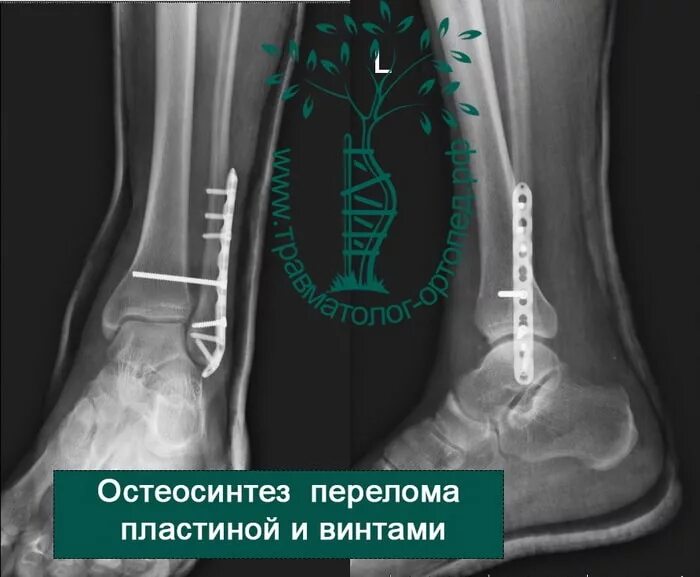

Лодыжка перелом смещение операция пластина